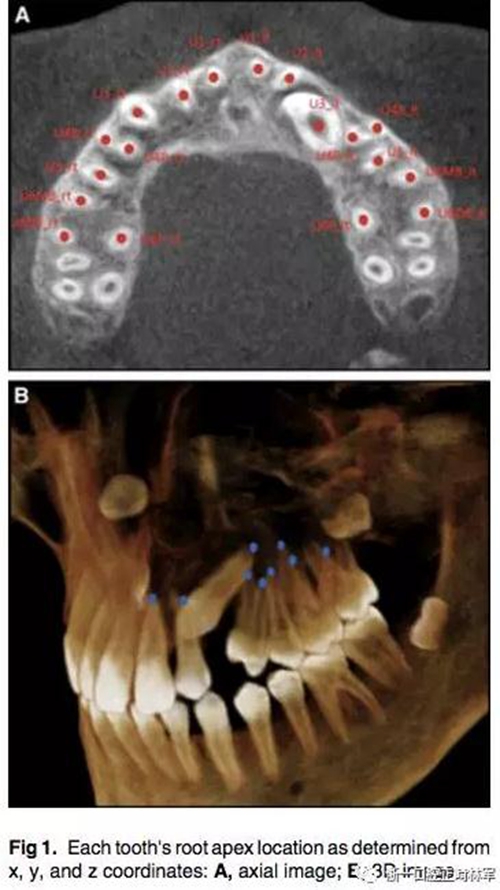

通過CBCT來確定尖牙牙根的具體位置,以x,y,z三維坐標(biāo)表示。我們定義在面中線上,鼻根點(diǎn)作為鼻額縫在額骨上的最前點(diǎn),CBCT掃描儀與腭平面水平。我們用3個(gè)標(biāo)志點(diǎn)(前鼻棘點(diǎn),兩側(cè)腭大孔的中心點(diǎn))來定位腭平面,將鼻根點(diǎn)坐標(biāo)定為(0,0,0),以此確定上頜牙齒根尖點(diǎn)的x,y,z的坐標(biāo)。由于上頜前磨牙和磨牙有2-3個(gè)牙根,因此將多個(gè)牙根的中心點(diǎn)作為根尖點(diǎn)。見Fig1.

為了測量根尖與牙根弓形的偏移程度,必須先確定牙根的平均位置。然后,測量每個(gè)牙根與弓形的距離,對于阻生尖牙,它的牙根平均位置為對側(cè)非阻生尖牙對稱得到,測量阻生尖牙的牙根與對稱而來的牙根位置之間的距離。